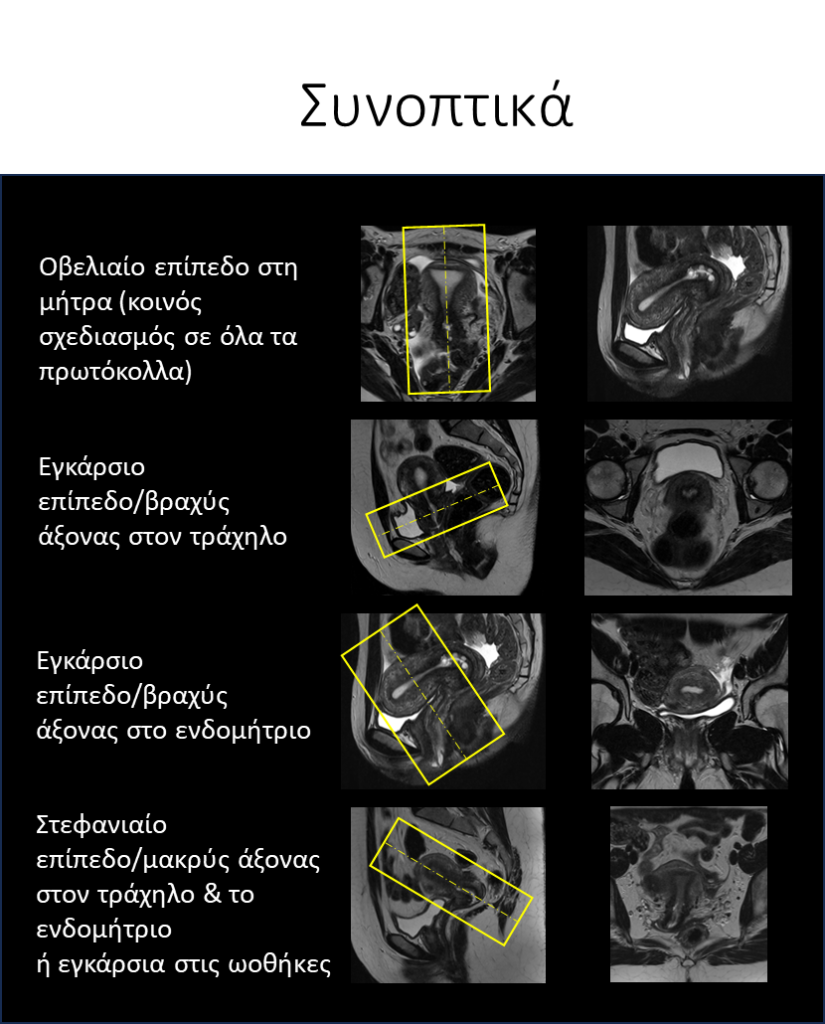

Λοξό εγκάρσιο και λοξό στεφανιαίο επίπεδο (axial & coronal oblique): Ανάλογα την περιοχή ενδιαφέροντος πρέπει να δίνεται και η κατάλληλη κλίση:

1. Ενδομήτριο: στην λοξή εγκάρσια ακολουθία δίνεται κάθετη κλίση με τον επιμήκη άξονα του ενδομητρίου, ενώ στην λοξή στεφανιαία δίνεται παράλληλη κλίση με τον επιμήκη άξονα του ενδομητρίου.

2. Τράχηλος: στην λοξή εγκάρσια ακολουθία δίνεται κάθετη κλίση με τον επιμήκη άξονα του τραχήλου, ενώ στην λοξή στεφανιαία δίνεται παράλληλη κλίση με τον επιμήκη άξονα του τραχήλου. Εάν υπάρχει ευδιάκριτη μάζα, οι τομές μπορούν να σχεδιαστούν βάσει των αξόνων της μάζας.

3. Ωοθήκες: στην λοξή εγκάρσια ακολουθία δίνεται παράλληλη κλίση με την μήτρα, ενώ στην λοξή στεφανιαία δίνεται κάθετη κλίση στη μήτρα.